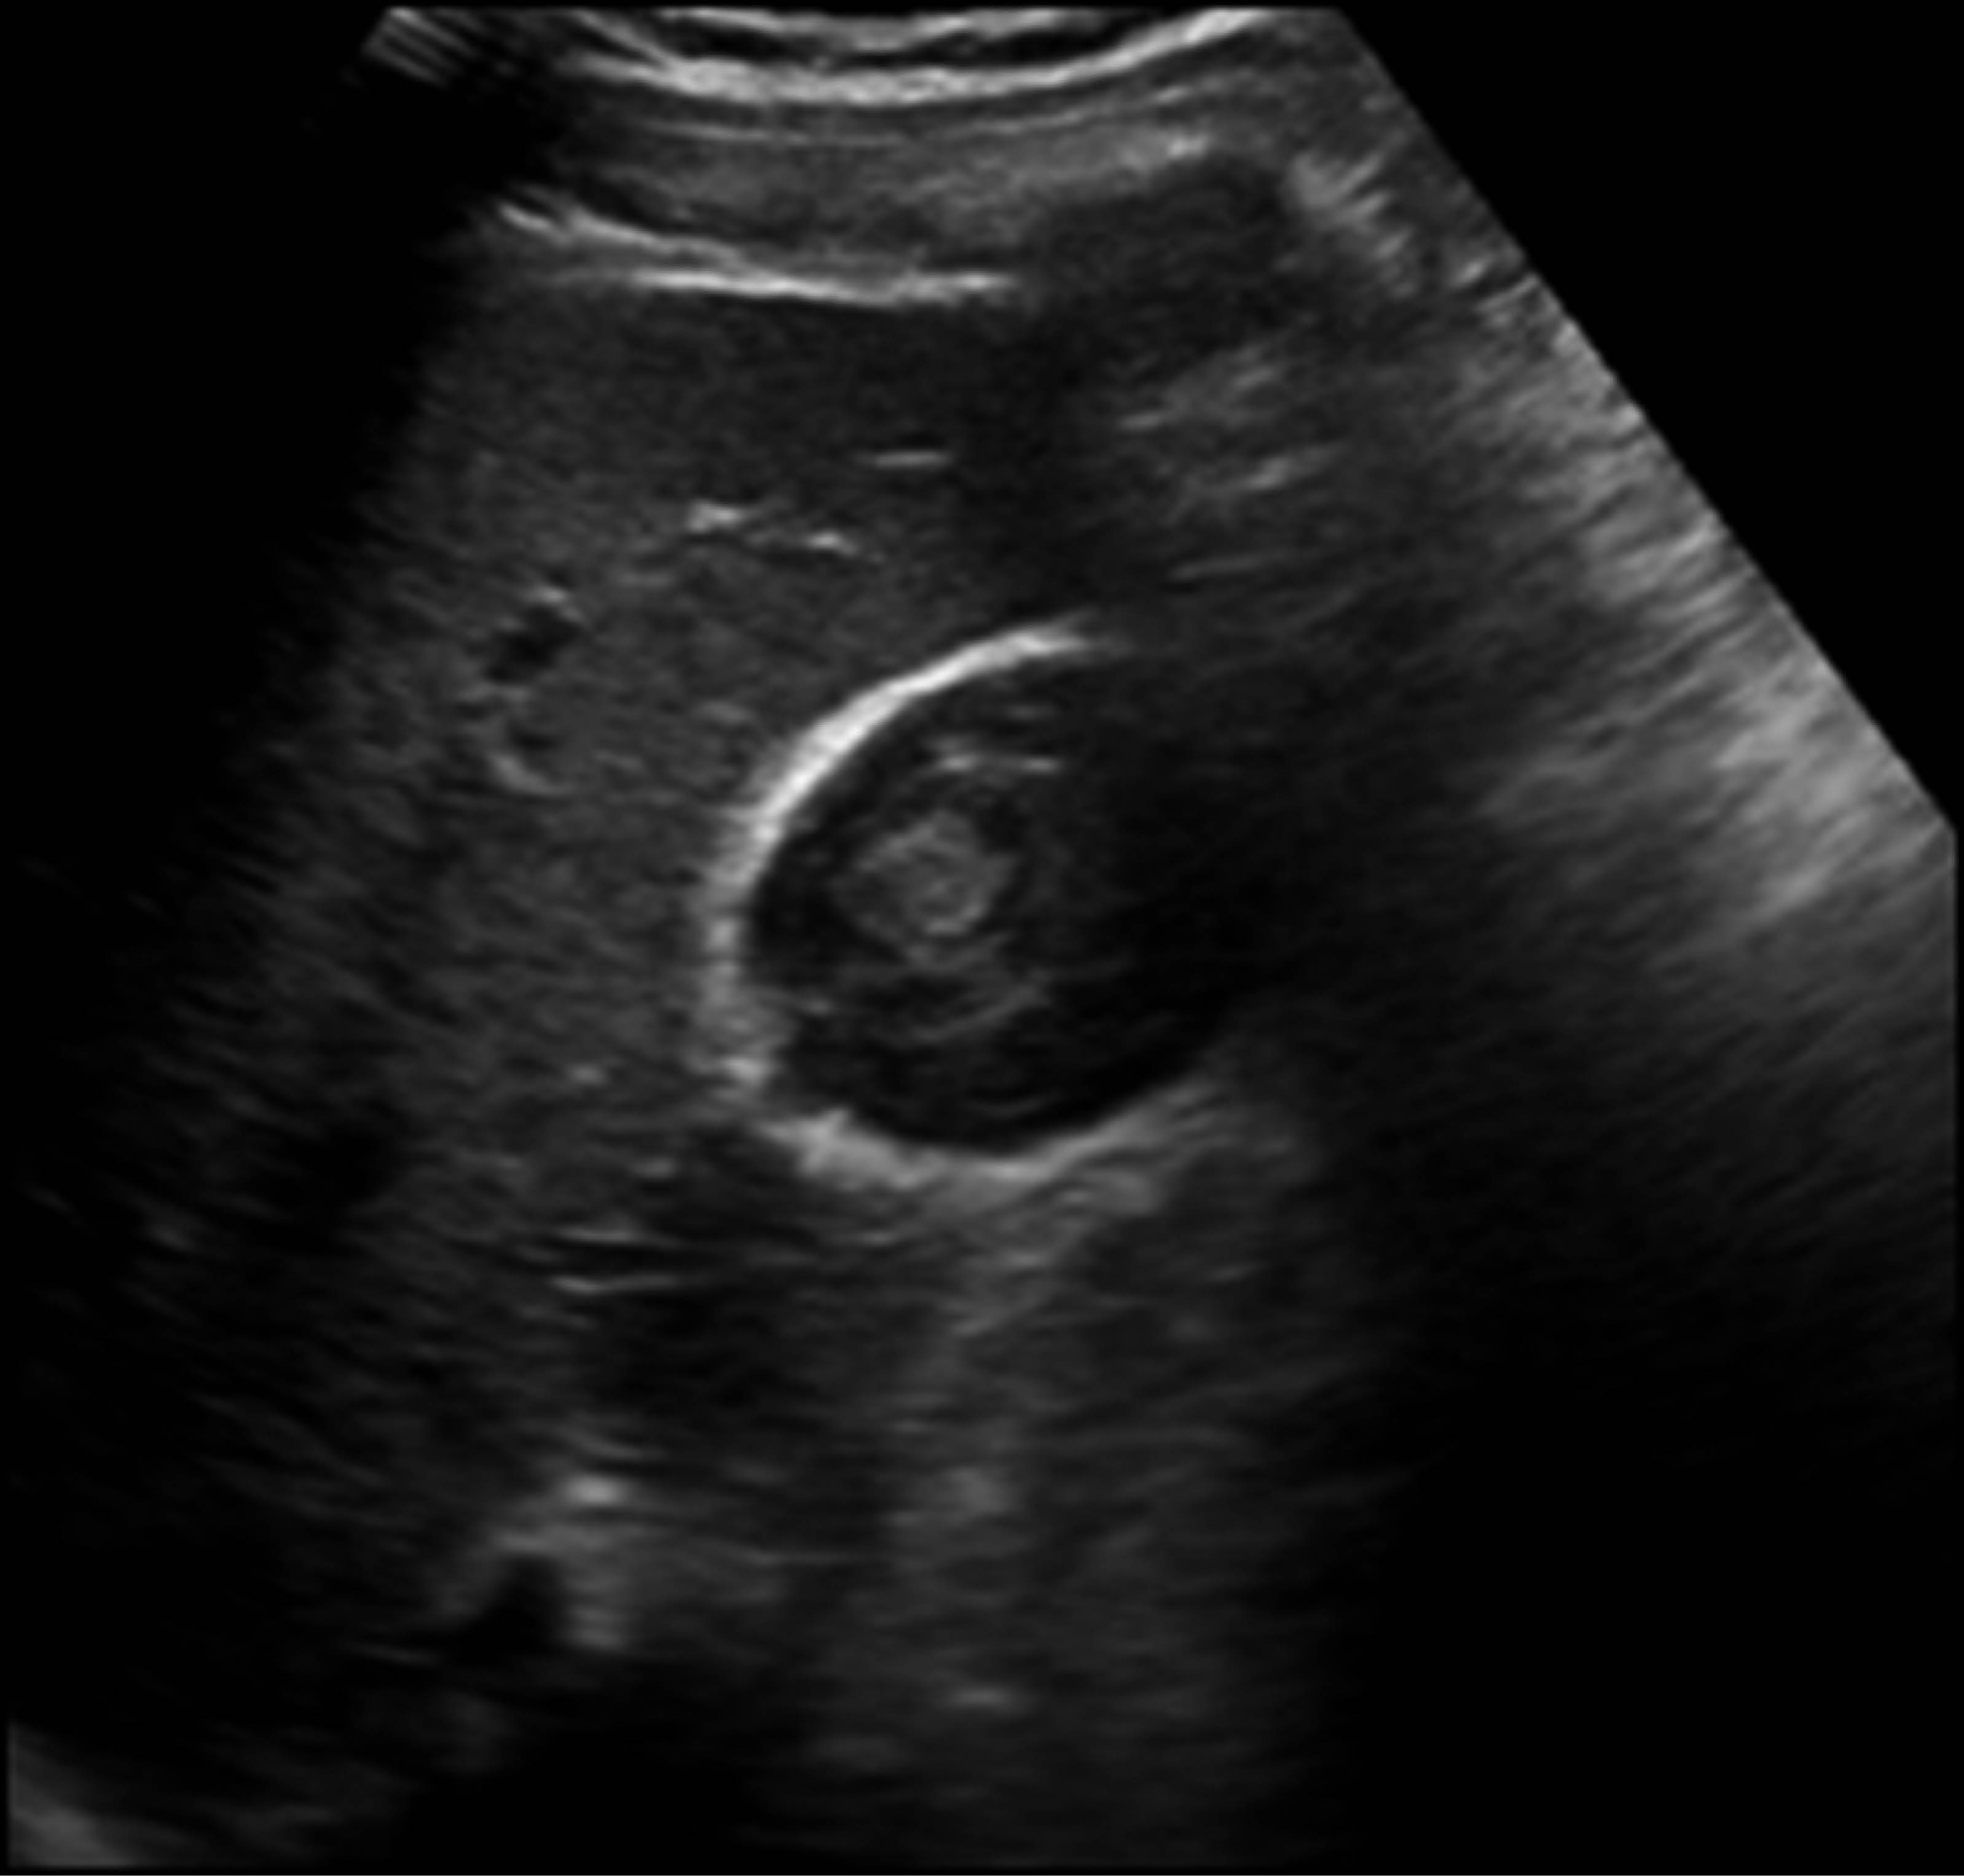

The patient continued without signs of peritoneal irritation or acute abdomen, although due to probable hemobilia, a computed tomography (CT) scan of the abdomen was requested 29 hours later that showed a hepatic laceration of segment V grade I of the AAST and a gallbladder measuring 81 × 44 × 48 mm with heterogeneous content, as described in Figure 3.

A pathognomonic sign of perforation is the extravasation of intraluminal contrast through the lesion associated with perihepatic fluid.1 Therefore, since the patient was stable with no evidence of shock that did not warrant an urgent surgical management, an abdominal CT scan was requested, reporting probable hematic content in the gallbladder, with no evidence of a continuity solution in the gallbladder wall.

Abdominal ultrasound can be effective by identifying hyperechogenic content in the gallbladder, peri vesicular free fluid, and continuity solution of the gallbladder wall. A hypoechoic, thickened edematous gallbladder wall despite prolonged fasting correlates with acute cholecystitis.4